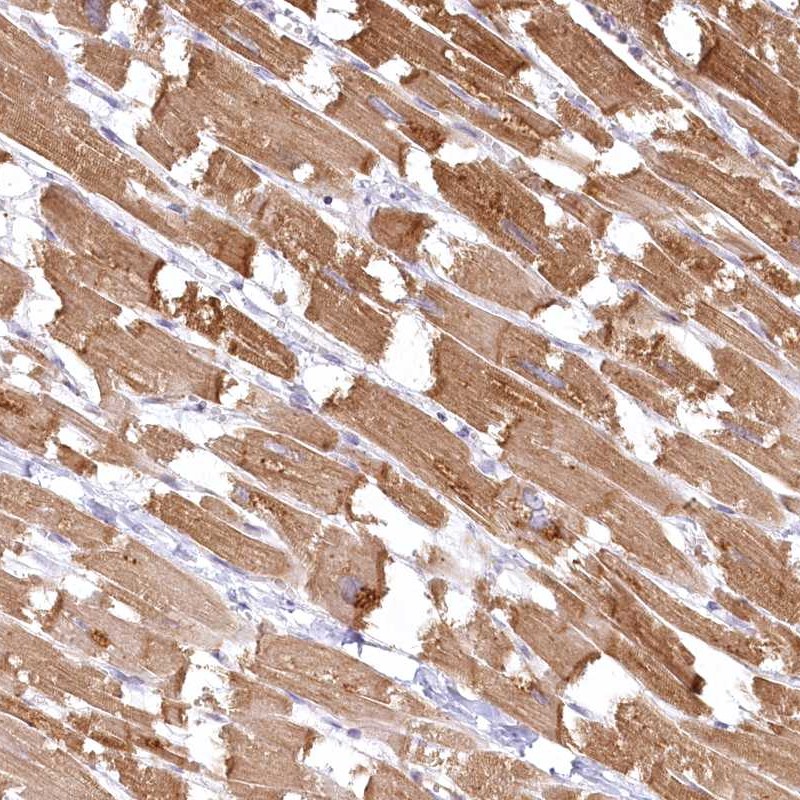

Immunohistochemical staining of human heart muscle shows moderate cytoplasmic positivity in myocytes.